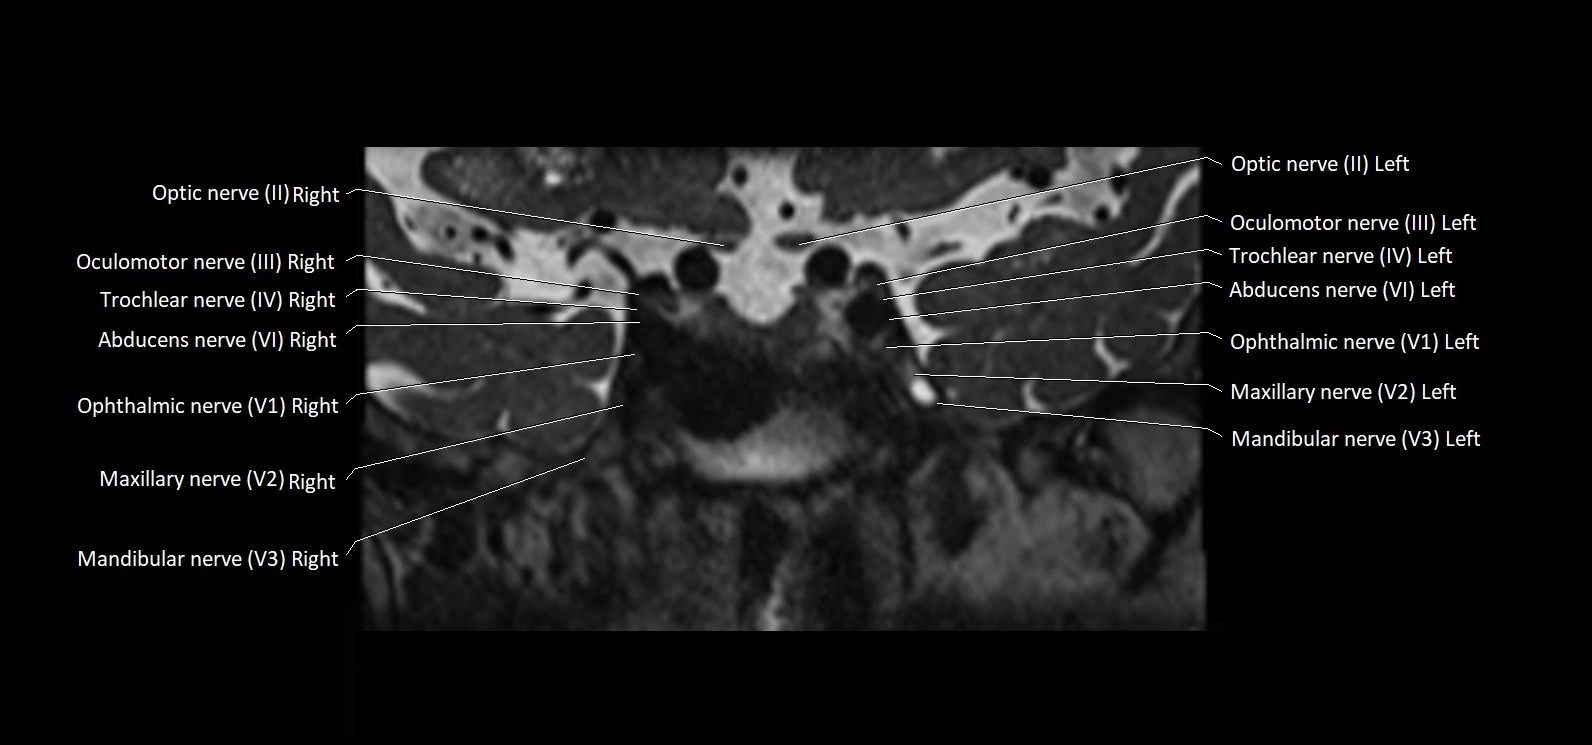

MRI Appearance

• The abducens nerve is a small, thin, linear structure

• Best visualized on high-resolution T2-weighted 3D MRI sequences (e.g., FIESTA or CISS)

• Seen as a hypointense (dark) line running from the brainstem at the pontomedullary junction, traversing the prepontine cistern, and entering Dorello’s canal under the petrosphenoidal ligament, then into the cavernous sinus, and finally the orbit

• May be challenging to visualize in standard MRI due to its small size

• Pathology may be inferred by absence, displacement, or enhancement of the nerve

MRI images

image